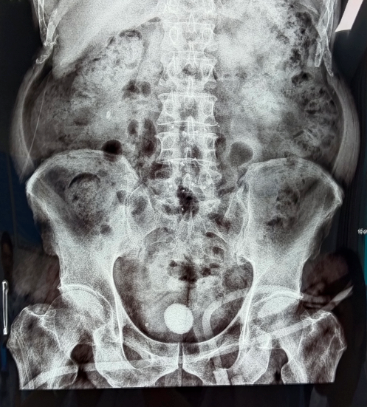

▲形态各异、大小不同、位置不同的泌尿系结石